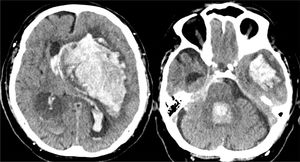

Caso 2Mujer de 65 años con antecedentes de HTA y cardiopatía isquémica en tratamiento con antiagregantes y antihipertensivos. Hemiplejia izquierda y disartria con un GCS de 14. En la TC craneal se evidencia pequeña hemorragia derecha en los ganglios de la base (fig. 5A), por lo que ingresa en la unidad de ictus para control. A las 4h presenta crisis hipertensiva, deterioro del nivel de consciencia con un GCS de 6 (O1-V1-M4) y anisocoria con midriasis derecha arreactiva. En una nueva TC se observa hemorragia masiva hemisférica derecha (fig. 5B), con signos de herniación subfalcial. Ingresa en la UCI y, dada la gravedad de la lesión, se descarta cualquier tipo de tratamiento. Se informa a la familia y al CT, quien comprueba que la paciente contaba con documento de instrucciones previas en el que manifestaba su deseo de ser donante de órganos, hecho que es comunicado a la familia, quien acepta continuar con CIOD y cumplir la voluntad de la paciente. A las 15h de su ingreso se confirma la ME. Donante de hígado y 2 riñones, que fueron trasplantados con resultado satisfactorio.